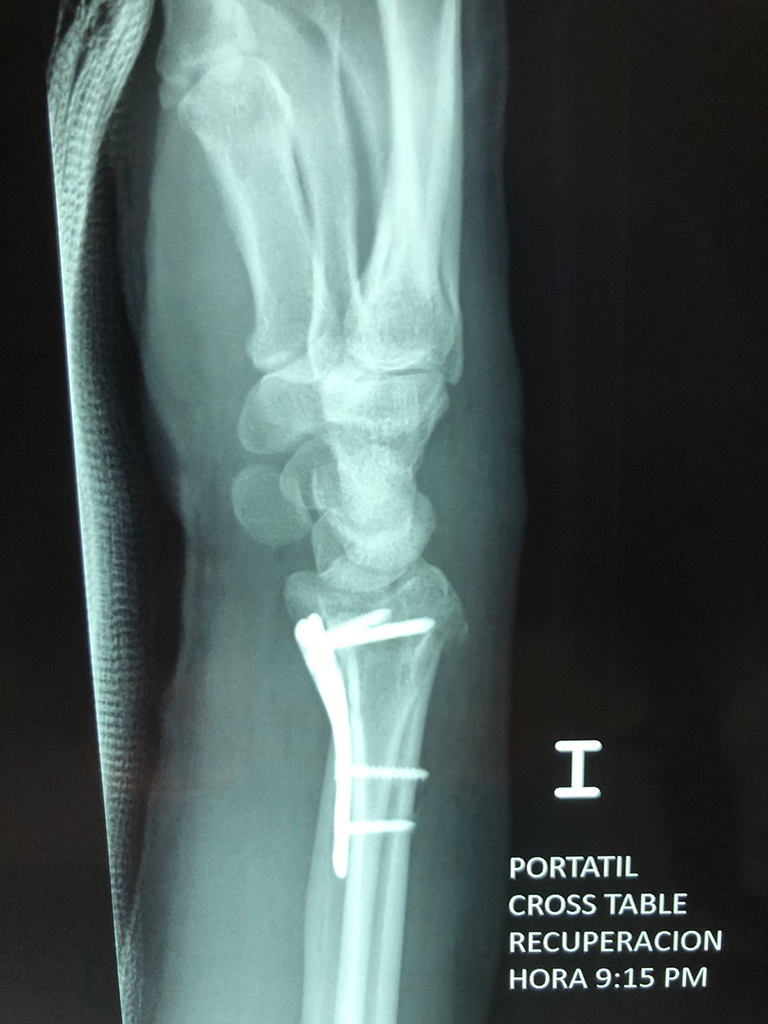

Los procedimientos más comunes en cirugía de la mano son aquellos destinados a reparar traumatismos, incluyendo lesiones de tendones, nervios, vasos sanguíneos, y articulaciones; huesos fracturados; y quemaduras, cortes, y otros daños de la piel.